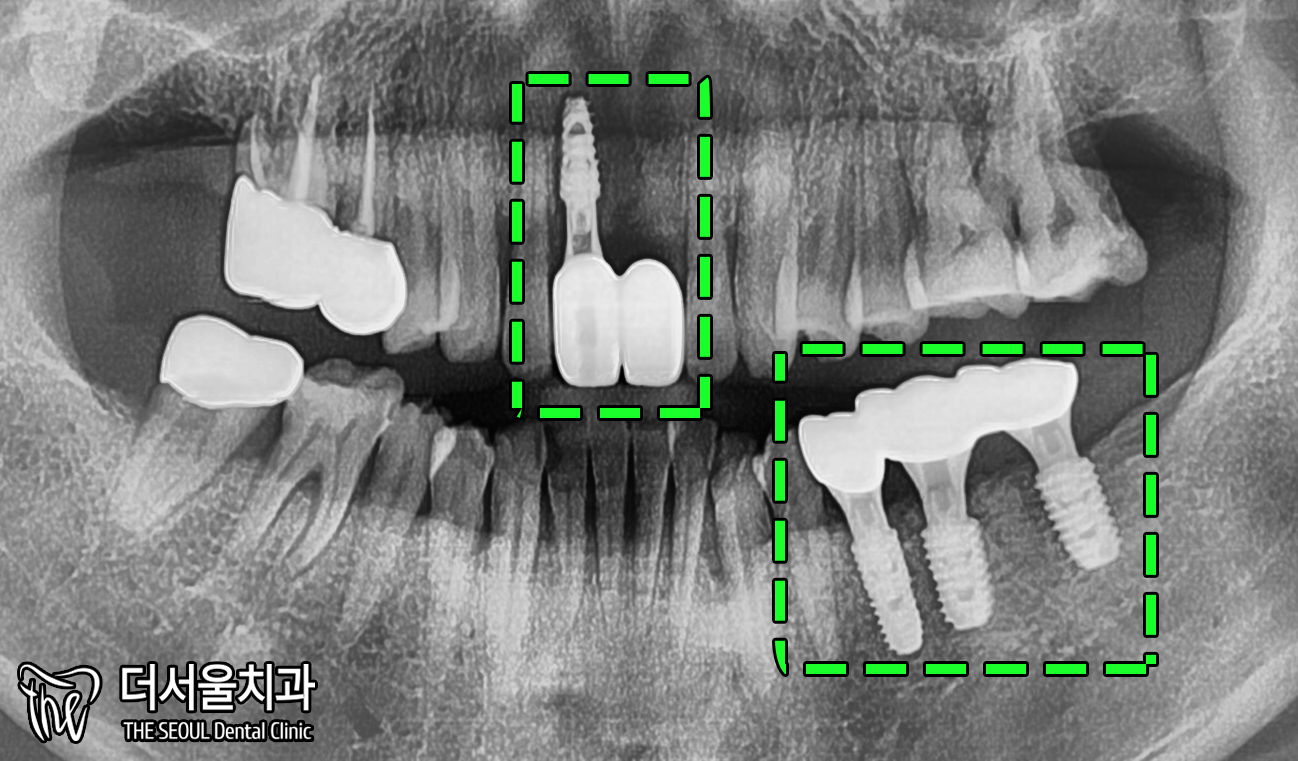

2. 엑스레이

X-ray 촬영본을 보면,

치아 뿌리에 염증이 발생한 것을

확인할 수 있습니다.

좀 더 자세히 보여드리겠습니다.

뿌리 쪽을 보면 시커멓죠?

염증이 있는 것을 알 수 있습니다.

이러니 흔들림이 나타날 수밖에 없구요.

아래 왼쪽 어금니 부분에도 마찬가집니다.

뿌리 끝은 아니지만,

중간 즈음으로 검게 변한 것을 볼 수 있습니다.

다행이었던 점은

두 곳에 나타난 염증이 그렇게 크지 않습니다.

때문에 바로 발치 후 즉시 식립이 가능합니다.

엑스레이로 한번 더 체크했을 때도

뼈와 잘 붙었습니다.